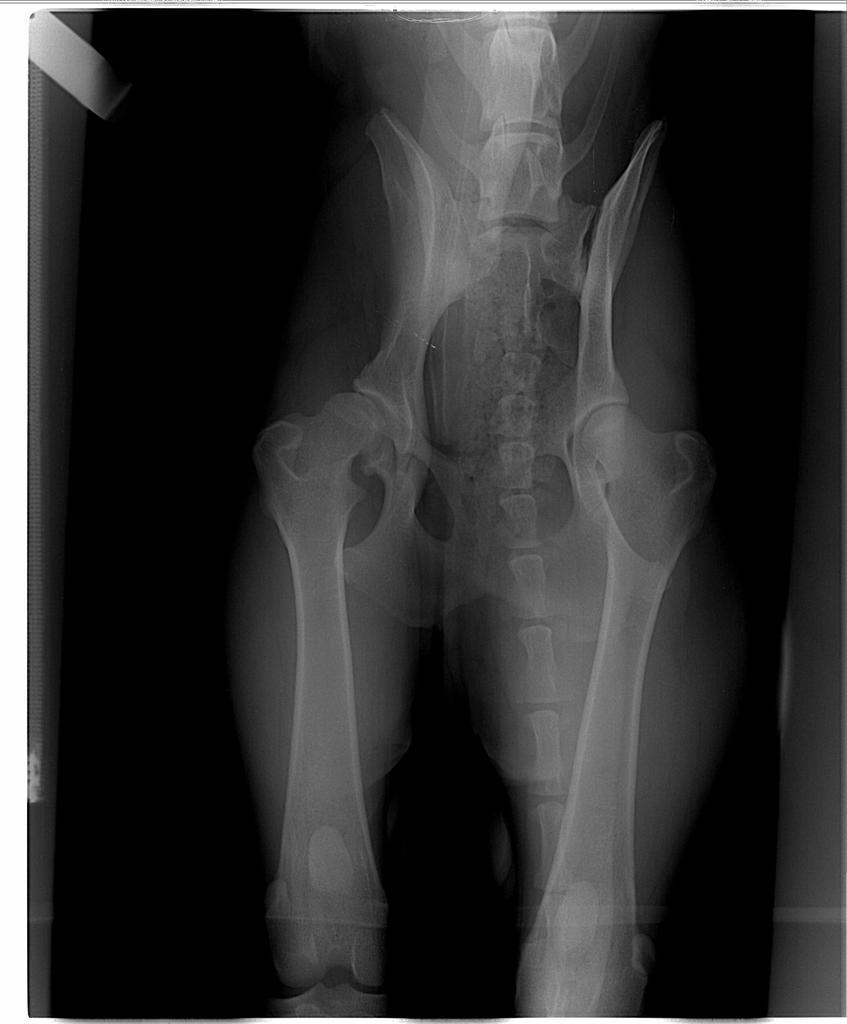

daga10011 Posted October 12, 2006 Posted October 12, 2006 Chcialam wam ku przestrodze opowiedziec jak niektorzy weci-chirurdzy przeswietlaja psy i jakie sa tego wyniki:roll: .Swego czasu w pewnej klinice przeswietlilam szczeniaka wowczas 5 miesiecznego -zeby sprawdzic biodra(juz o tym bylo,ale przypomne,zeby rozjasnic sytuacje o ktorej potem napisze)-wet stwierdzil dysplazje i chcial ciac-ja pojechalam dla pewnosci do Wawy i przeswietlilam psa ponownie-kilku wetow obejrzalo zdjecia-te z naszej kliniki i te z Wawy-na jednym dysplazja na drugim nie:roll: ..Nie przeprowadzilam operacji-dzis pies ma sie dobrze i byl przeswietlony 2 miesiace temu-bez okreslania przez speca stopnia dysplazji(bo jest kastratem) -wyglada to na B-sa luzy,ale bez znieksztalcen i pies nie ma problemow ruchowych,wbrew temu co nasz wet twierdzil,ze tak bedzie:roll: .a za chwile cd.... Quote

daga10011 Posted October 12, 2006 Author Posted October 12, 2006 no i ciag dalszy... Przeswietlilam psa z odzysku( w tej samej klinice)-jedno biodro ideal,drugie budzace watpliwosci-B lub C-nie zdziwilam sie w sumie,bo pies mial wowczas fatalny ruch i lapy(teraz ma o niebo lepsze,odkad go odchudzilam i spaceruje czesto:roll: )..Ale po miesiacu przeswietlilam tez tam suke-wet twierdzil,ze biodra ideal(no chociaz raz w tej klinice:roll: ) i wyslalam zdjecie do Wroclawia do dr.Siembiedy-wrocilo mi HD/C:crazyeye: .Wkurzylam sie troche,rozpatrzylam sterylizacje ale pomyslalam,ze to niemozliwe-bo suka byla badana w wieku 12 miesiecy i miala zdecydowane HD/A(w olsztynie)-w koncu wczoraj pojechalam z suka i psem do Wroclawia osobiscie i powiedzialam sobie- co bedzie,to bedzie-ale wiem,ze spec mi psa ulozy dobrze..Jaki wynik?????Pies HD/A i suka HD/A:roll: . Uwazajcie gdzie przeswietlacie swoje psy:roll: Quote

LAZY Posted October 13, 2006 Posted October 13, 2006 Niestety ale nasze prześwietlenia wg standardów FCI są bardzo subiektywne w ocenie. Jedno i to samo zdjecie oglądane przez różnych wetów moze dawac różne wyniki. Czasami jest to kwestia ulożenia psa (ale to raczej u szczeniaków, gdzie układ kostny jeszcze nie jest dobrze wykształcony),a czasami poprostu subiektywnymi odczuciami. Czytalam niejednokotnie o tym, ze na jednym RTG jest dysplazja na innym nie. Jednak wedlug dr Janickiego (dość dobry fachowiec z Warszawy) nie ma takiej sytuacji, ze pies miał dyplazję i ona zniknęła na drugim zdjęciu, według niego to jest zawsze błąd w odczycie zdjęcia przez weterynarza. Zaznacza, ze sam ma u siebie w szufladzie kilka RTG psów, które dostały HD/A a on by ocenił to jako stawy dysplastyczne. I jaki wniosek? Sam system prześwietlen nie jest idealny. Niestety... Quote

Nor(a) Posted October 13, 2006 Posted October 13, 2006 LAZY napisał(a):Jednak wedlug dr Janickiego (dość dobry fachowiec z Warszawy) nie ma takiej sytuacji, ze pies miał dyplazję i ona zniknęła na drugim zdjęciu, według niego to jest zawsze błąd w odczycie zdjęcia przez weterynarza. No nam tak dysplazja znikneła w "cudowny" sposób w ciągu 24h :p ..no bo jak ktoś układa psa z nogą krzywo do środka i noga nie dośc że poza stawem to jeszcze luzy jak stąd do.. Szczecina (sorry LAZY ;) :cool3: ..tak mi sie powiedziało). Mamy też na papierze "fajną" diagnozę wraz z zaleceniem dostarczenia psa na stół operacyjny - zdrowego psa. Wystawioną przez fachowca. Nic mnie już nie zdziwi w tym temacie. Quote

daga10011 Posted October 13, 2006 Author Posted October 13, 2006 sylrwia napisał(a):Ojej a ja zastanawialam sie nad zorbieniem przeswietlenia stawow u młodego. Skad mam wiedziec, ze pies bedzie dobrze ułożony?? Jak to sprawdzić? pies musi byc w rynience i nogi musza byc wyciagniete na prosto rownolegle-tak przeswietlal nam dr.siembieda..wczesniejsze przeswietlenia byly bez rynienki.Pies musi byc calkowicie bezwladny-najmniejszy ruch da zafalszowane zdjecie;) Quote

Nor(a) Posted October 15, 2006 Posted October 15, 2006 sylrwia napisał(a):Bardzo dziękuje za informacje. To my na razie musimy poczekać bo młody za młody na razie. Choć dziwne to bo jedna wetka jak młody miał 7 miesięcy to juz chciała go profilaktycznie prześwietlać. :cool1: Obejrze najpierw jak to zamierzją robić czy w rynnie czy bez. Jak wet-specjalista w tej dziedzinie to prześwietli bez rynny..ale to wyższe szkoła jazdy a specjalistów mało ;) . Nasze 2 psy byly prześwietlane w Warszawie bez rynny (łącznie 4 albo 5 RTG). Wyszło wszystko bardzo dobrze tak jak powinno być. Tylne łapy wyciągane na prosto za pomocą...sznurka. Trochę to szokująco wygląda jak ktoś pierwszy raz takie cos widzi ;) Quote

Flaire Posted October 17, 2006 Posted October 17, 2006 Szami napisał(a):Żeby zdjęcie "wyszło" dobrze "Znieczulenie" jest konieczne ! Tak przynajmniej powszechnie uważa się w Polsce ;-). Ja miałam w USA robione zdjęcie przez doskonałego specjalistę po tym, jak polscy "specjaliści" ponoć wykryli dysplazję u mojej suki (na zdjęciu robionym pod narkozą). Ten amerykański spec robi zdjęcia bez znieczulenia (i takie zrobił Misi). Uspokoił mnie, że Misia dysplazji nie ma i potwierdziła to OFA (organizacja w USA atestująca psie biodra). To było 3 lata temu. Dzisiaj Misia ma prawie 6 lat, biega w agility, w życiu nie kulała. Prześwietliłam ją ponownie kilka miesięcy temu przy okazji sterylizacji, żeby się upewnić, że w stawach nie dzieje się nic co by nakazywało zmniejszyć intensywność treningów - w końcu panna mi się starzeje. ;-) No i biodra ma nadal piękne, żadnych zmian zwyrodnieniowych, dysplazji brak. Tak więc narkoza nie jest konieczna do zrobienia dobrego zdjęcia - ale umiejętności - i owszem. ;-) Quote